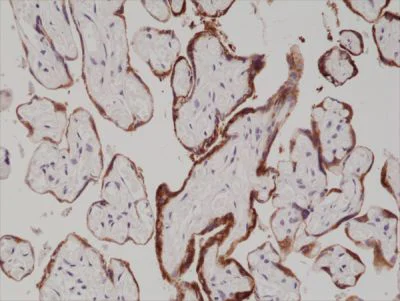

Immunohistochemistry (Formalin/PFA-fixed paraffin-embedded sections) - Anti-hCG antibody [RM330] (AB238319)

Formalin-fixed, paraffin-embedded human placenta tissue stained for hGC using ab238319 at 1/1000 dilution in immunohistochemical analysis.